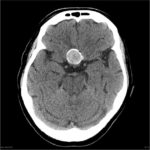

Case of the Day: Brain Mass on CT

What is your diagnosis? A. Craniopharyngioma or B. Aneurysm

Answer - Click here